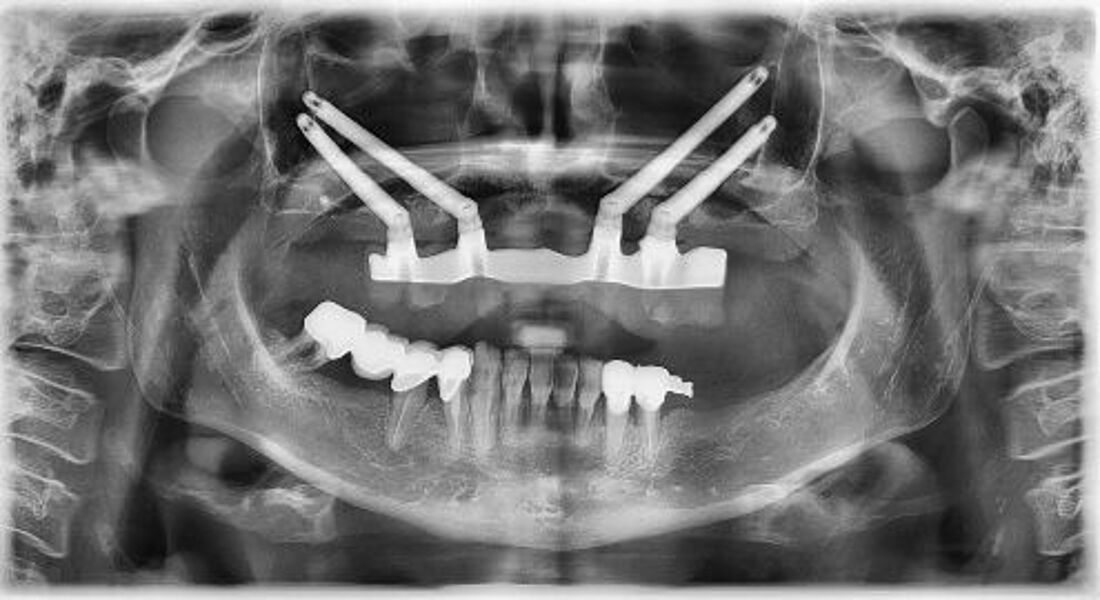

Im vorliegenden Fall wird über eine 62-jährige Patientin mit nicht erhaltungsfähiger Restbezahnung sowie ausgeprägter Oberkieferkammatrophie berichtet. Um eine gewünschte Sofortversorgung mit Sofortbelastung des Oberkiefers zu ermöglichen, wurden vier Zygoma-Implantate inseriert.

Zeitschrift: ZBW – Zahnärzteblatt Baden-Württemberg

Ausgabe: 12/2020, Seiten 32 – 35

Autoren: PD Dr. Michael Korsch, M.A., Dr. Abdel-Karim Mamar